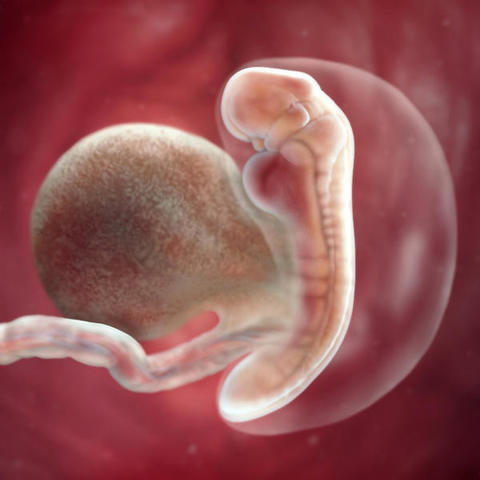

• Semana 4 - Comienza el periodo embrionario

Semana 4 - Comienza el periodo embrionario

Se caracteriza por el desarrollo de los órganos del futuro bebé. El embrión ya está implantado en el útero, con un tamaño de entre 0,36 y 1 mm de longitud.

Inicio de la Organogenesis -

El grupo de células se diferencia en tres láminas u hojas, que darán lugar a los futuros órganos:

- Ectodermo: que dará lugar al sistema nervioso.

- Endodermo: dará lugar al tracto gastrointestinal, páncreas, hígado y tiroides.

- Mesodermo: formará los huesos, músculos y sistema sanguíneo.